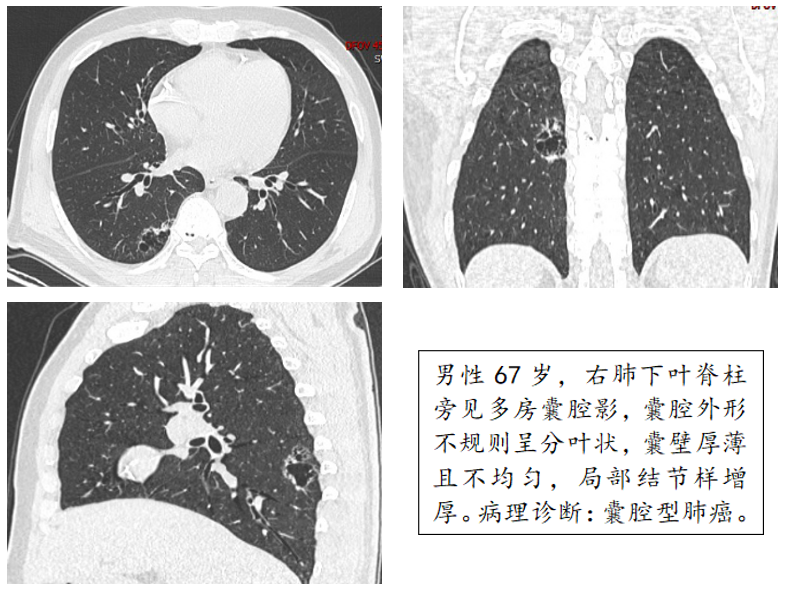

囊腔型肺癌是一类发病率较低,CT影像上不同于表现为软组织结节或肿块的一般的肺癌,影像表现以薄壁囊腔伴大小不等软组织壁结节为特点的少见肺癌类型,容易误诊为肺大泡、肺囊肿、空洞等病变。需要密切随访复查胸CT,及时手术切除。